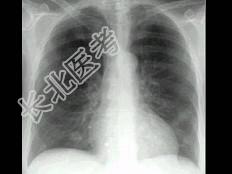

- 单项选择题多发性骨髓瘤患者出现咳嗽,咳痰, 气急,胸片检查发现病变后行CT检查如图, 最可能的诊断为 ( )